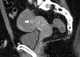

Struma ovarii

A struma ovarii (literally: goitre of the ovary) is a rare form of monodermal teratoma that contains mostly thyroid tissue, which may cause hyperthyroidism.Despite its name, struma ovarii is not restricted to the ovary. The vast majority of struma ovarii are benign tumours; however, malignant tumours of this type are found in a small percentage of cases. [Source: Wikipedia ]